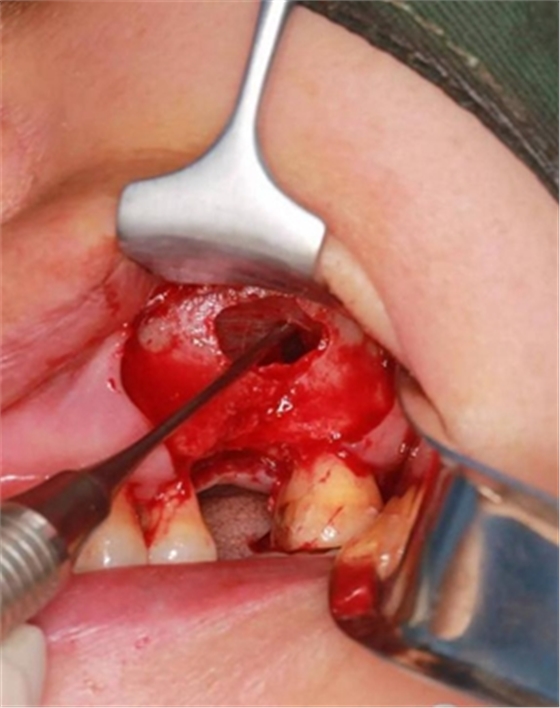

大家好,我是梁老師的助理小依。由于梁老師每天手術(shù)檔期安排較滿,加上經(jīng)常出差講課,沒有時間整理病例 。為了方便大家更及時的了解梁老師最新手術(shù)動態(tài),以后將由我為大家整理并推送梁老師最新經(jīng)典案例。案例文字旁白少,但圖片會盡量完整展示手術(shù)全過程,供大家學(xué)習(xí)參考。有任何問題,可以留言,梁老師會親自為大家解答。感謝大家對梁老師的支持和關(guān)注!